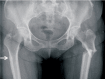

Nonsurgical Treatment Strategies after Osteoporotic Hip Fractures

Osteoporosis is a metabolic disease that is increasing in prevalence as people live longer. Because the orthopedic surgeon is frequently the first and often the only physician to manage patients with osteoporotic hip fractures, every effort should be made to prevent future fractures. A multidisciplinary approach is essential in treatment of osteoporotic fractures. Basic treatment includes calcium and vitamin D supplementation, fall prevention, hip protection, and balance and exercise programs. Currently available pharmacologic agents are divided into antiresorptive and anabolic groups. Antiresorptive agents such as bisphosphonates limit bone resorption through inhibition of osteoclastic activity. Anabolic agents such as parathyroid hormone promote bone formation.